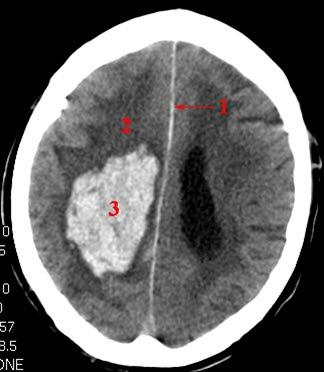

CT-bilde av hjerneblødningStrålebelastningen er større enn ved de fleste vanlige røntgenundersøkelser, men denne ulempen oppveies av at behandleren får mye større utbytte (mer informasjon) fra CT - man får rett og slett bedre bilder. Moderne CT-maskiner har betydelig reduserte stråledoser i forhold til eldre maskiner.

CT av hjernen betegnes på fagspråket for cerebral CT. Bildene som tas brukes til å fremstille hjernevev, hinner og blodårer inne i hodet. Bløtvev med ulik tetthet kan skilles fra hverandre, og i hjernen kan f. eks. hjernebark og hjernemarg (grå og hvit substans) skilles fra ryggmargsvæsken. CT er godt egnet til å vise f.eks. akutte blødninger i hjernen, men når man skal vurdere hjernevev er MR en langt mer detaljert undersøkelse.

Bildene vises i ulike gråtoner. Jo lysere skygge, jo høyere tetthet har vevet eller strukturen. Bein blir hvitt, mens luft blir svart. Tilførsel av røntgenkontrast via blodet kan gi bedre bildeinformasjon, f.eks lar store blodårer seg lettere fremstille etter tilførsel av kontrast i årene.

Hjerneblødninger kan være vanskeligere å se, særlig dersom det er gått noe tid (dager, uker) siden blødningen skjedde. En blodpropp i hjernen (lager et hjerneinfarkt) kan overses dersom det har gått for kort tid, dvs. få timer siden skaden skjedde. Pasientbevegelser reduserer kvaliteten på bildene.

En lang rekke forandringer i hjernen kan påvises ved CT. De hyppigste sykdommene man kan finne er hjerneblødninger og skader på skallen, hjerneskader som følge av hjerneslag (blødning eller blodpropp, trombose), svulster, spredning fra kreftsykdom annet sted i kroppen, betennelser og demensforandringer.